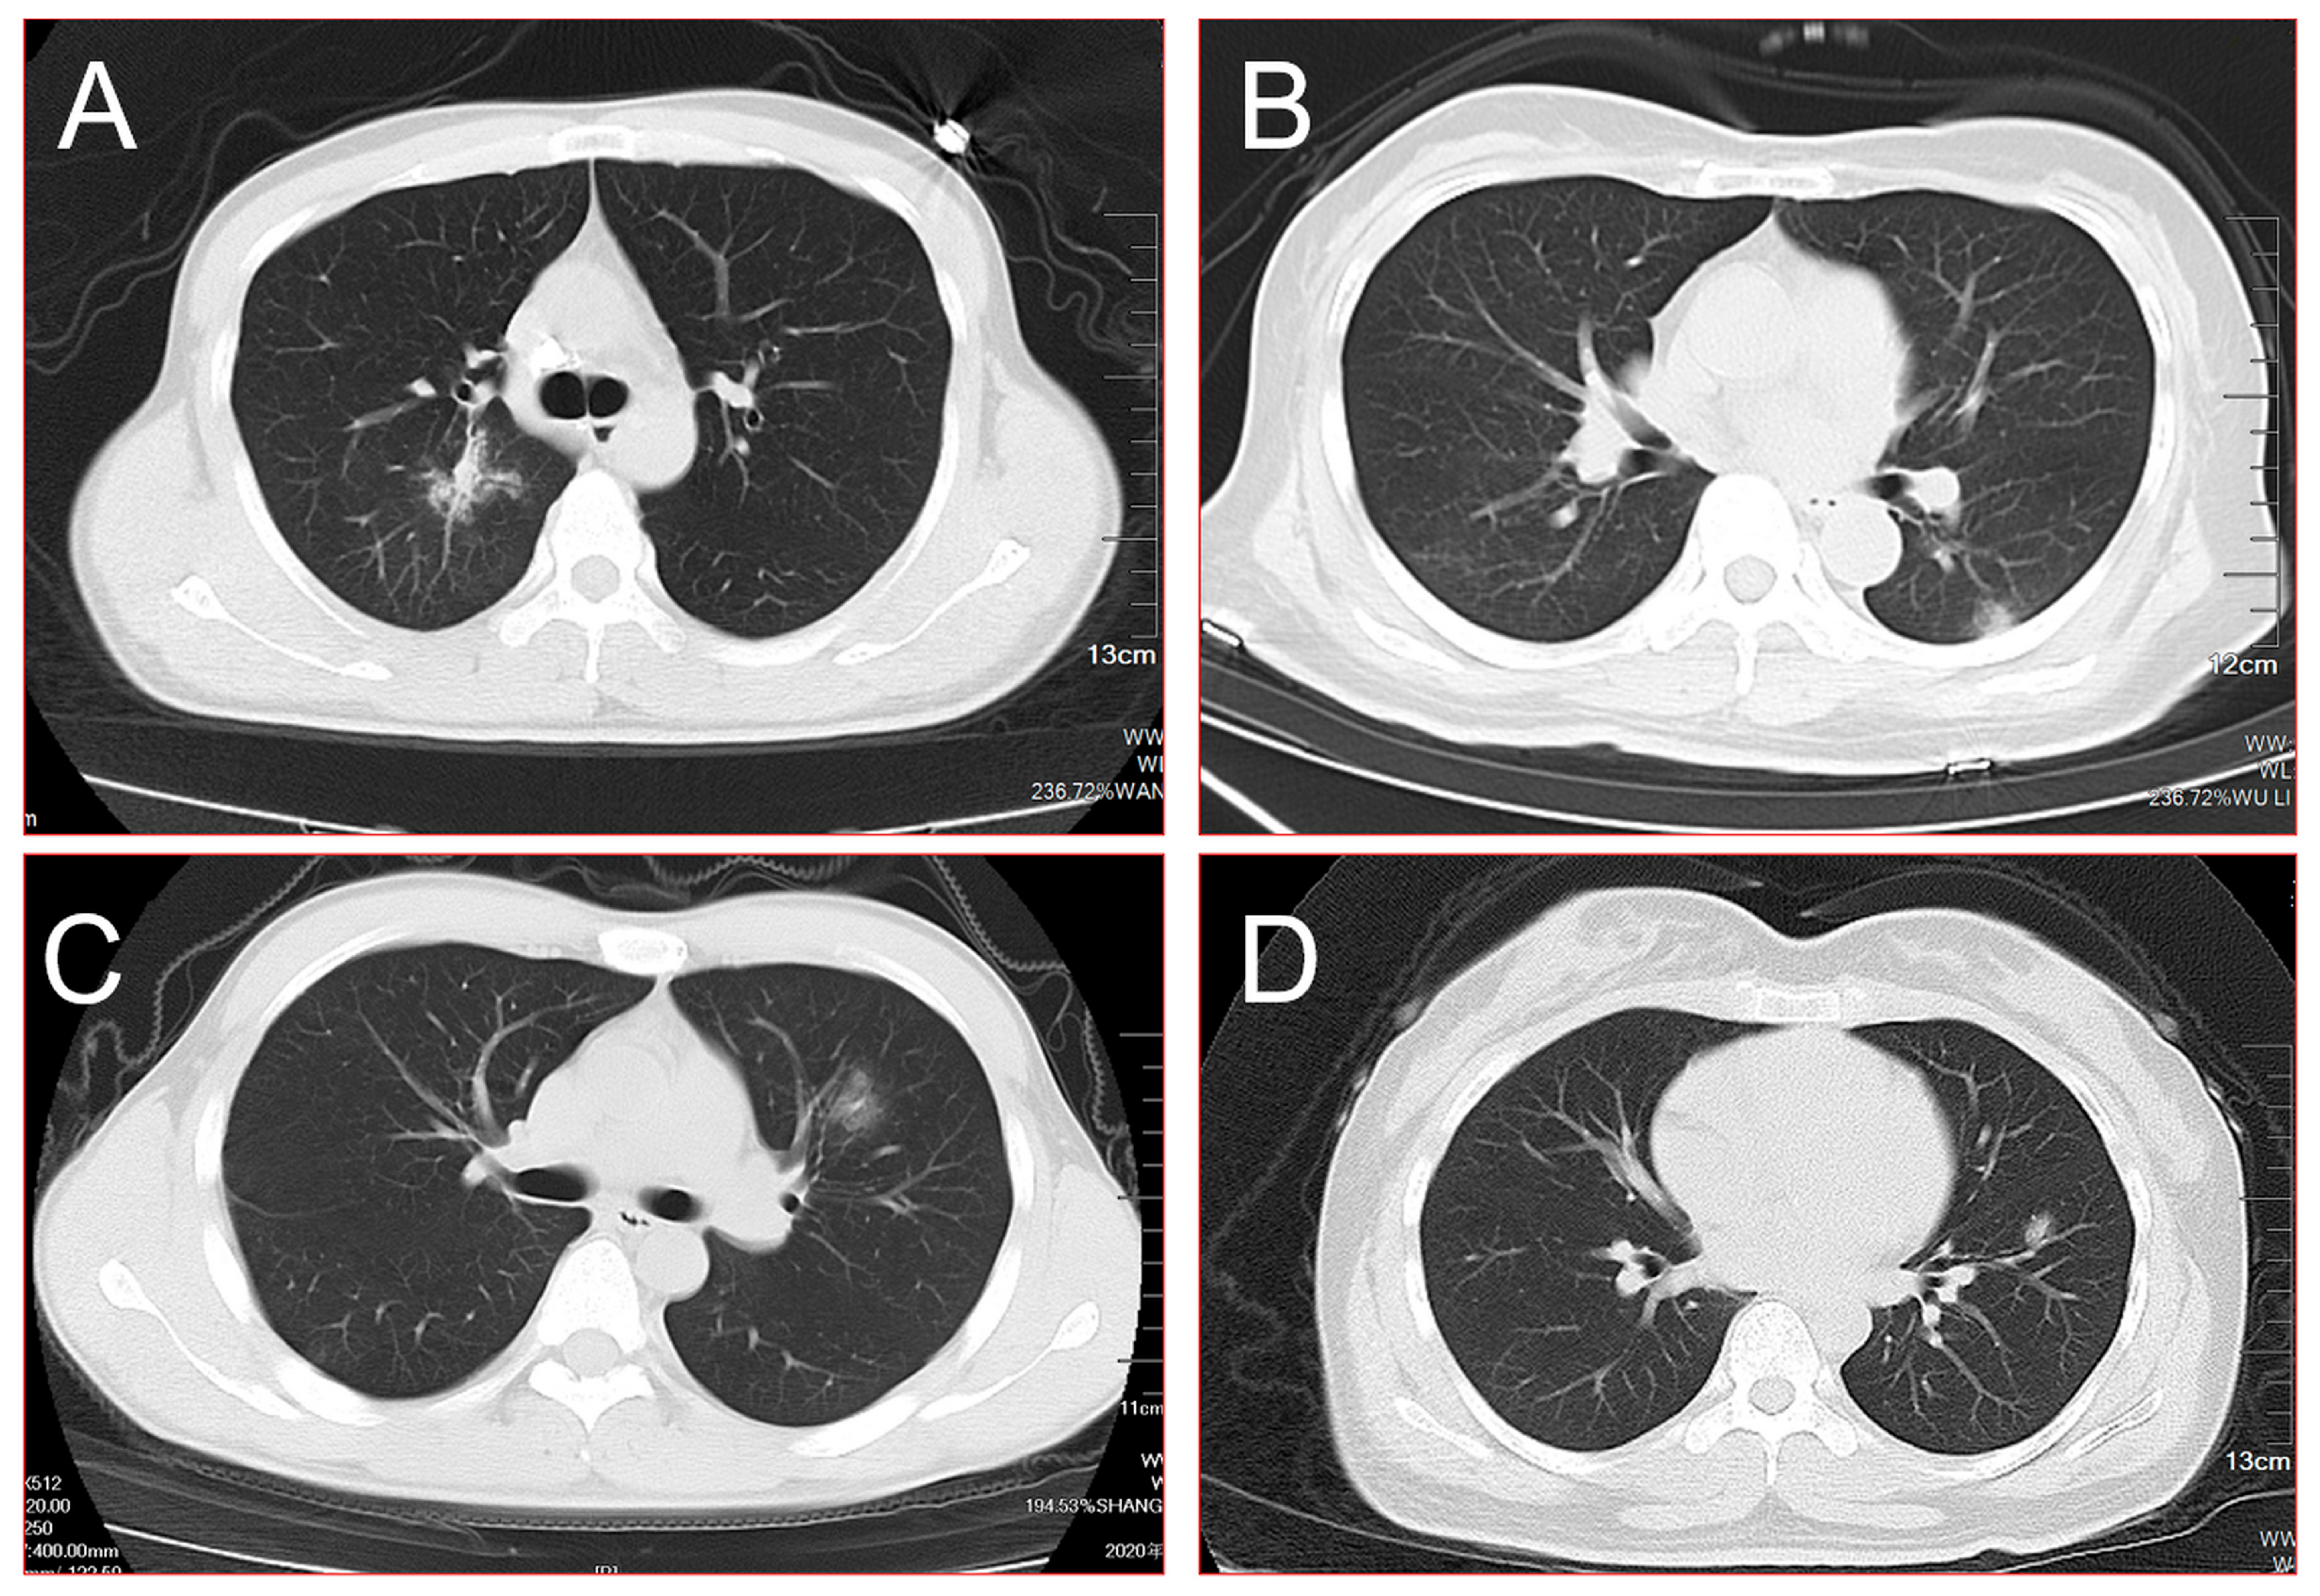

| Distribution | |

| Periphery distribution | 15 (71.4%) |

| Central distribution | 6 (28.6%) |

| Patterns of the SPN | |

| Burr sign | 16 (76.2%) |

| Lobulated sign | 13 (61.9%) |

| Pleural indentation | 9 (42.9%) |

| Smooth edges | 5 (23.8%) |

| Cavity | 3 (14.3%) |

| Density of the SPN | |

| Pure ground-glass nodule | 13 (61.9%) |

| Mixed ground-glass nodule | 8 (38.1%) |

| Diameter of the SPN | |

| <10 mm | 3 (14.3%) |

| 10 mm–20 mm | 8 (38.1%) |

| >20 mm | 10 (47.6%) |

| AI results | |

| High-risk nodules | 16 (76.2%) |

| Medium-risk nodules | 5 (23.8%) |

| Progression of SPN | |

| No development | 5 (23.8%) |

| Develop to one side of lungs | 4 (19.0%) |

| Develop to both sides of lungs | 9 (42.9%) |

| Develops to all lobes of bilateral lungs | 3 (14.3%) |